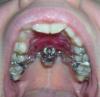

Libelle Опубликовано 28 июня, 2009 Поделиться Опубликовано 28 июня, 2009 Здравствуйте! Была на консультациях у нескольких ортодонтов. 2-е говорят удалять 8-ки, ставить обычную керамику, возможно придется носить лицевую дугу, сроки 2-2.5 года. еще вариант у других докторов - ничего не удалять(либо удалять 8-ки не по ортодонтическим соображениям, а т.к. растут в щеку и не имеют антагонистов), ставить Дэймон3, расширять челюсть, что ситуация не криминальная, сроки 1год -1.5 года. Последний доктор понравилась, решила лечиться у нее, сделали слепки, и по проведенным расчетам он меня прямо обескуражила - удаляем 4-ки, выравниваем зубки и правим прикус, если 4-ки оставлять, то зубы выровним, челюсть расширим, но прикус не исправим....и еще увеличится сагиттальная щель (оказывается у меня еще и щель). Из 6 врачей никто не говорил удалять 4-ки, но и расчетов никто не проводил, только осмотр и снимки. Боюсь, что остальные врачи после проведения расчетов также придут к удалению 4-к. Начиталась в нете, что удаление 4-к вытянет лицо с возрастом. Одна девушка носит так называемую бабочку, и за три месяца сдвинула челюсть верхнюю назад, удалив восьмерки, уже семерки на их место сдвинулись, хотя у нее щель намного больше. Хотя неудобная вещь жутко. Еще прочитала, что при задвижении верхней челюсти назад уменьшится десневая улыбка, она меня тоже беспокоит. С 8-ми мне расставаться не жалко, тем более там кариес и растут криво, но последний врач говорит, что они все равно не в прикусе и на ситуацию не повлияют......Подскажите еще варианты лечения в моем случае. С Уважением Юлия http://s59.radikal.ru/i166/0906/22/d9c2cf954e89t.jpg http://s61.radikal.ru/i172/0906/a2/986c2ab6ecc7t.jpg http://s44.radikal.ru/i104/0906/88/dc3a8bfe1ef1t.jpg http://i035.radikal.ru/0906/33/96bb6398cedbt.jpg http://s42.radikal.ru/i096/0906/5e/4a3fc7cab63ct.jpg http://i007.radikal.ru/0906/30/03391b5158a4t.jpg http://i042.radikal.ru/0906/ea/0e9f17470455t.jpg Ссылка на комментарий

Libelle Опубликовано 28 июня, 2009 Автор Поделиться Опубликовано 28 июня, 2009 Еще фото.http://i035.radikal.ru/0906/34/48f9827928b8t.jpg http://i027.radikal.ru/0906/00/51fb9fcca2b6t.jpg http://s46.radikal.ru/i111/0906/90/a6b1439a2ab6t.jpg http://s57.radikal.ru/i155/0906/30/d2d4669c415dt.jpg http://i077.radikal.ru/0906/a3/4107ff444a6bt.jpg т.е. вариант с 8-ми вообще отпадает??? или можно попробовать, но будет более длительное лечение. Мне из 6-ти врачей никто не собирался удалять 4-ки, говорили вобще без удаления(повторяюсь). Или они не видели слепков и не делали расчетов??? Ссылка на комментарий